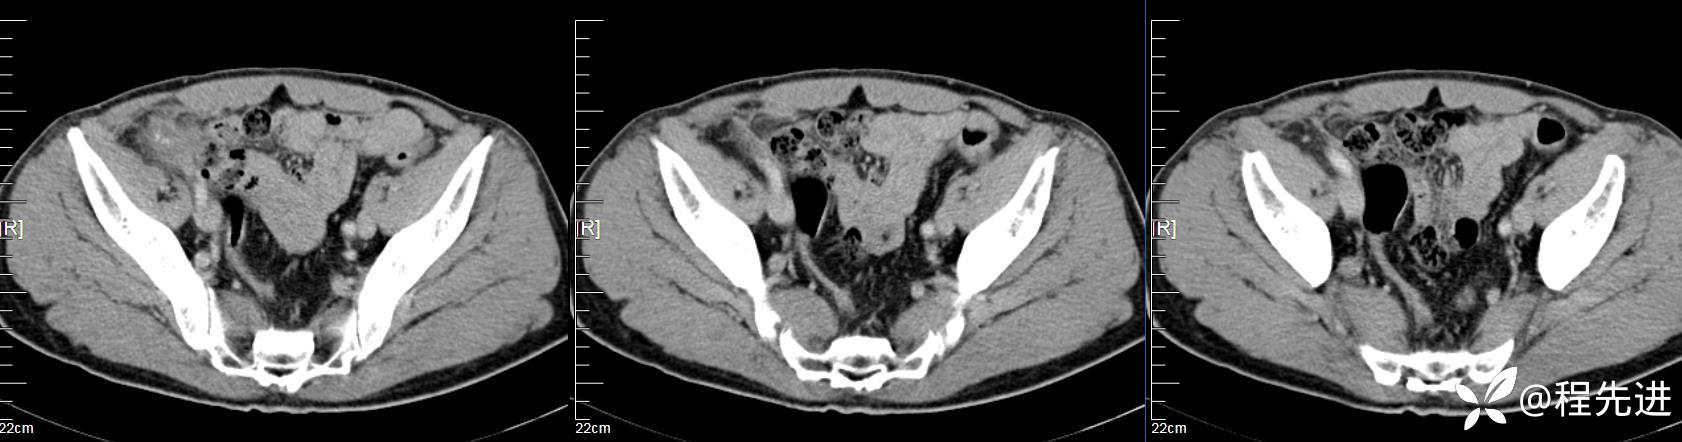

【患者信息】:男,61岁

【现病史及既往史】:右下腹部疼痛伴腹胀2天

【影像检查】